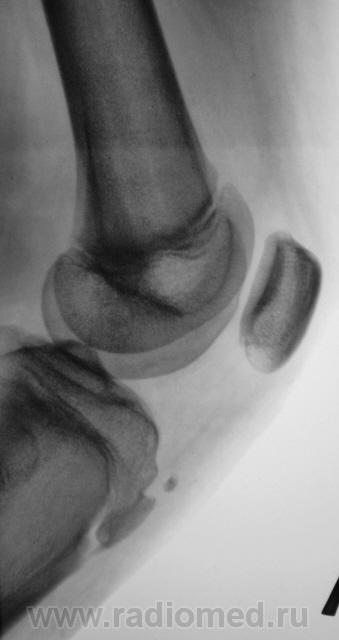

Пациент был направлен на рентгеновское исследования обоих коленных суставов по поводу болеши "Осгут-Шлаттера"

Нет, я был не прав, что утверждал, что на прямой рентгенограмме бугристость не отображается. Мы, на пленке уже вообще не работаем, оказалось, что на "цифре" на прямой отображается и ох, как хорошо.

Кроме остеохондропатии бугристостей у пациента явная латеропозизия надколенников и бугристостей большеберцовых костей, что свидетельствует о дисплазии мыщелков бедренных костей, вероятнее всего клинически проявляющаяся болями в переднем отделе коленных суставов (под надколенниками).

Интересно было бы посмотреть на аксиальные снимки надколенников. Явно ожидается уплощение медиальных мыщелков и межмыщелковых углублений бедренных костей.